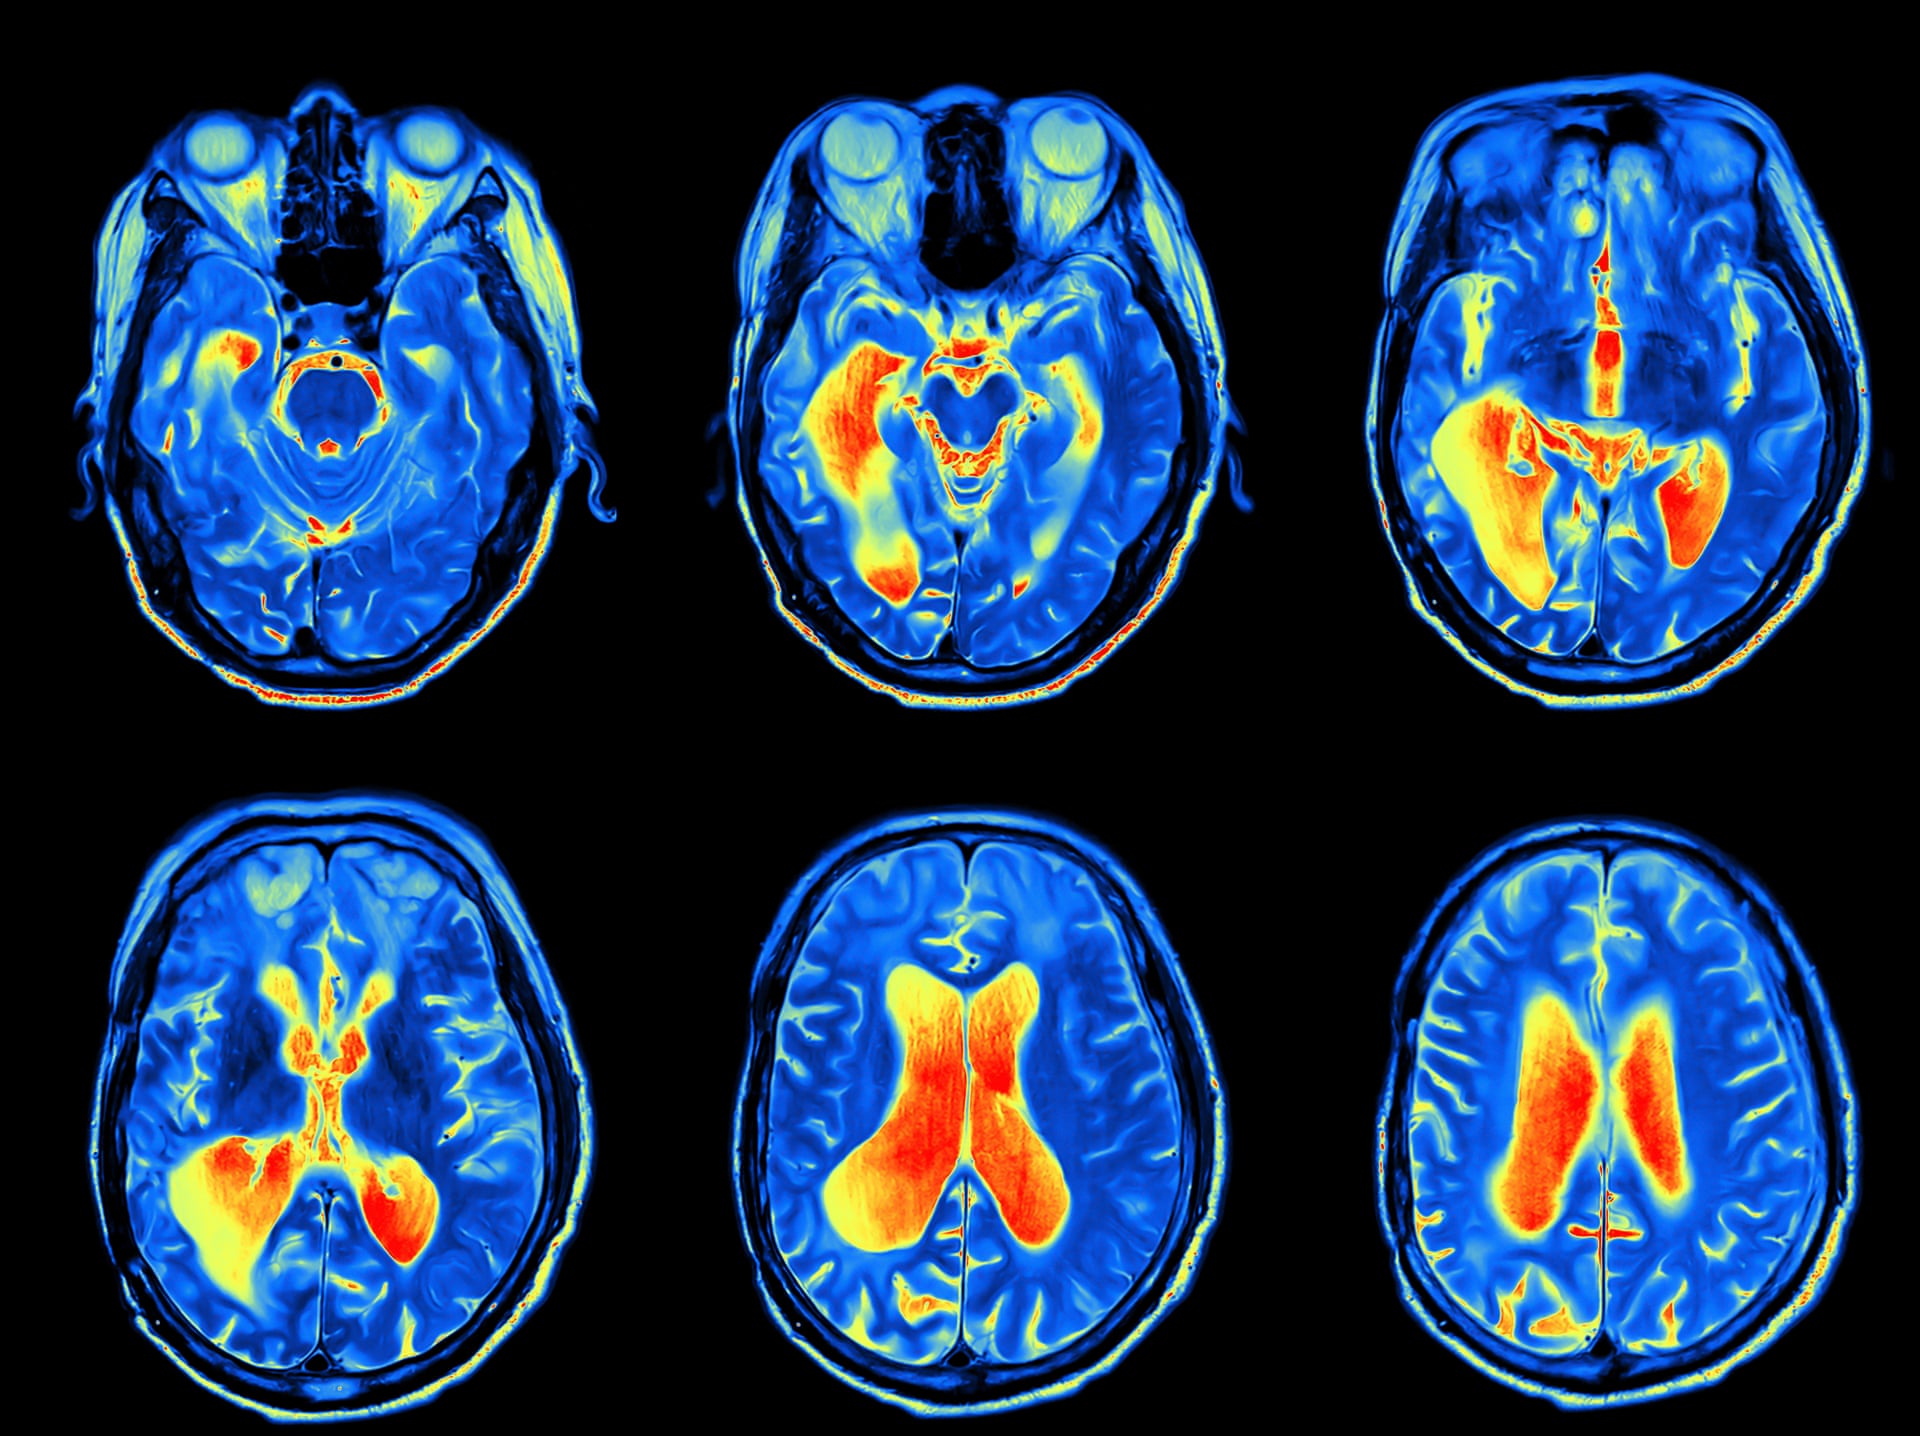

对大脑的MRI 扫描。